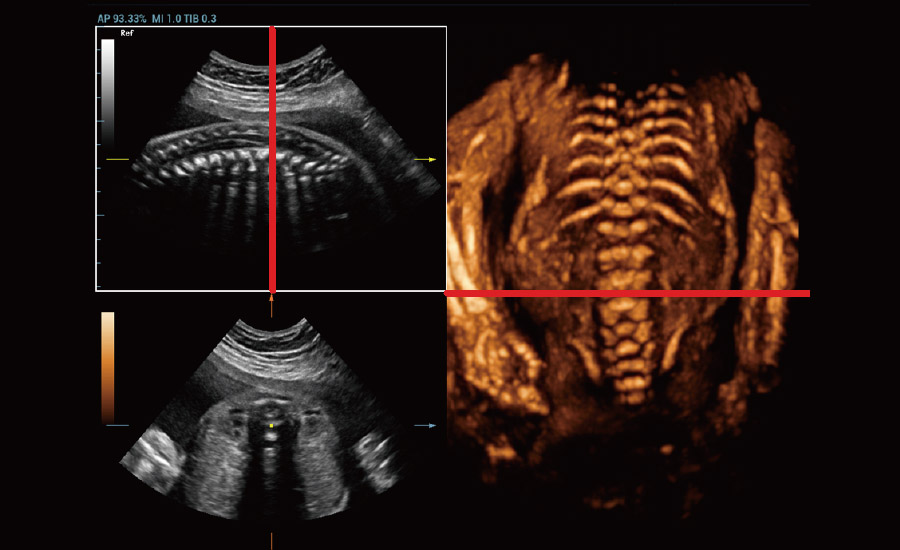

UMA (Ultra-Micro Angiography)

The innovative technology breaks the bottlenecks of traditional Doppler imaging. With ultra-high spatial resolution and flow sensitivity, it allows detecting super-subtle and super-slow flow perfusions, thereby extending the clinical application of qualitative and quantitative ultrasound evaluation in fetal brain, kidney, placenta, endometrium, ovary, etc.

Combining advanced algorithms and domain-specific knowledge, the innovative Smart Scene solution enables auto identification of tissue characteristics and provides organ-specific diagnosis with full-stack intelligence. Based on auto scenario identification, the solution not only realizes smart 2D scanning with auto settings and measurements, but also delivers 3D full-stack intelligence in every step from volume imaging optimization to the difficult 2D plane acquisition, and quantification throughout whole procedure. It helps a lot in reducing the dependency on clinical skills, while increasing diagnostic accuracy, confidence and efficiency.